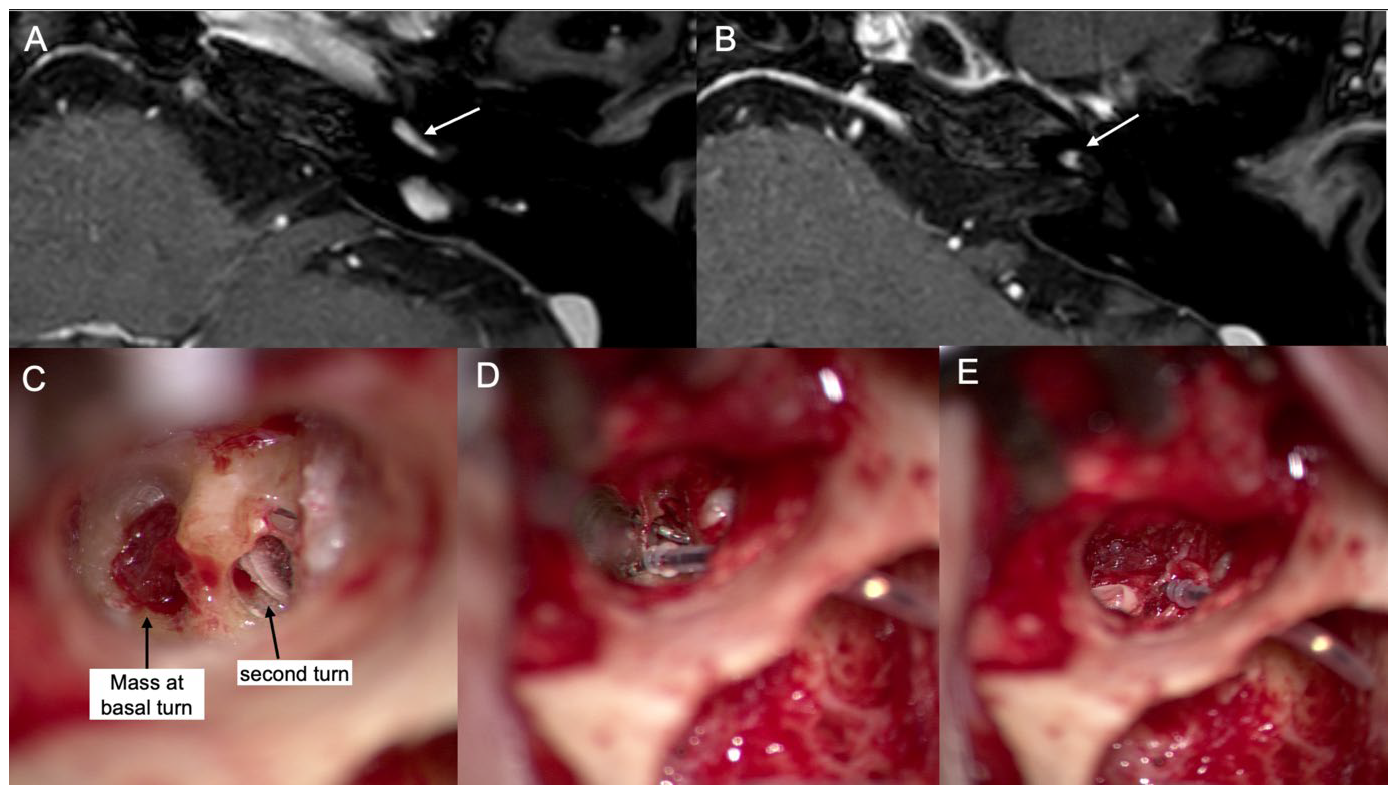

3.3. Case 3